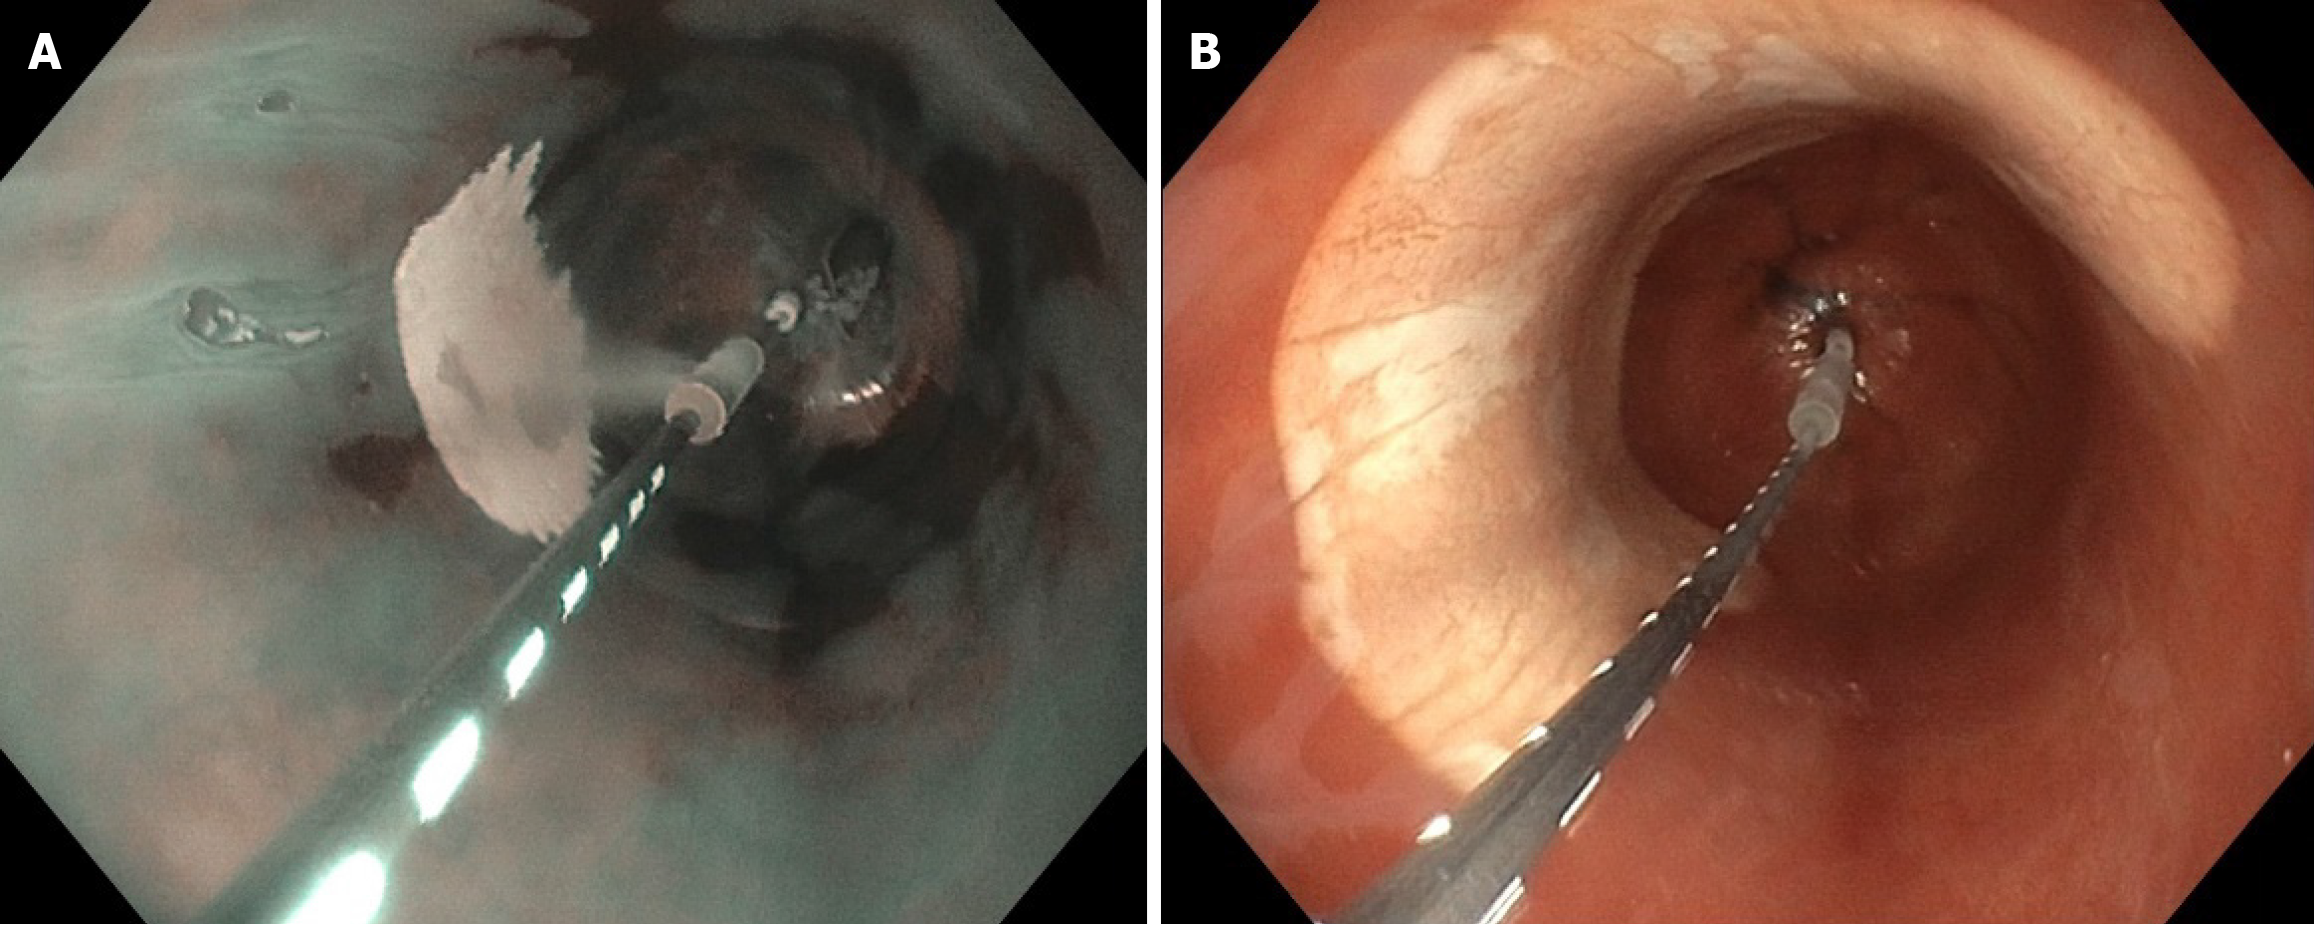

Figure 1 Cryoballoon ablation treatment in the esophagus.

A: Endoscopic view of treatment with the C2 focal cryoballoon catheter; B: Endoscopic view of treatment with the C2 cryoballoon 180° catheter.